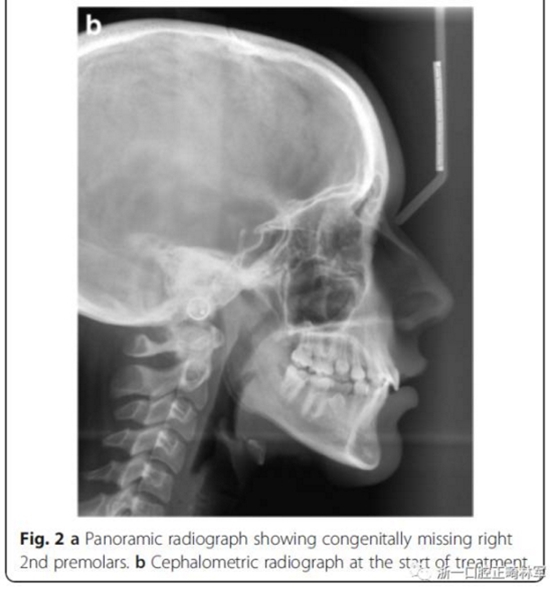

患者面型對(duì)稱(chēng),面上下比例對(duì)稱(chēng),輕度凸面型,鼻唇角正常;

右側(cè)II類(lèi)磨牙關(guān)系和尖牙關(guān)系,左側(cè)I類(lèi)磨牙關(guān)系和尖牙關(guān)系;

深覆合,前牙輕度不齊,下中線(xiàn)右偏2mm;

上下頜右側(cè)第二乳磨牙存,其余乳磨牙已脫落;

影像學(xué)檢查,右側(cè)第二前磨牙和所有第三磨牙先天性缺失;

頭側(cè)分析,骨性I類(lèi)關(guān)系,高角型